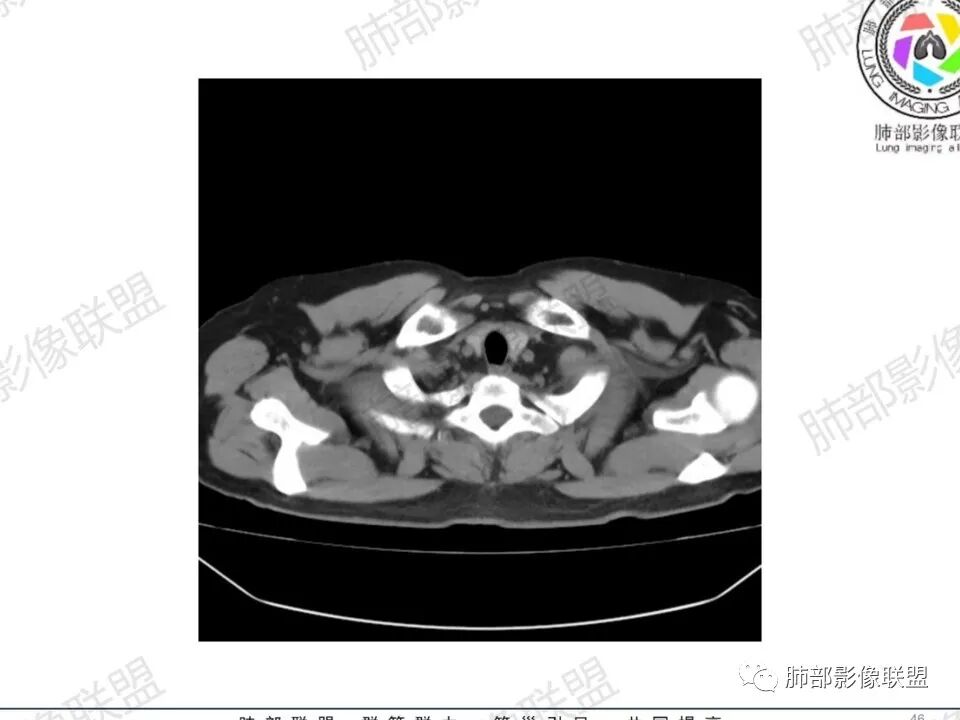

男,45岁,左手指红肿疼痛两天,右侧胸壁疼痛伴发热12小时入院。患者急性起病,胸部CT示双肺多发结节,部分伴空洞,空洞壁较光滑,右侧胸腔积液,考虑感染性病变,金葡菌加SPE可能

中年男性,左手中指及胸壁疼痛伴发热来诊,影像见双肺多发结节,胸膜下分布为主,部分结节可见空洞,边缘模糊。左肺上叶尖后段结节较大。右肺下叶后基底段不张实变,右侧叶间裂及右侧胸腔积液,右侧侧胸膜肥厚。考虑金葡菌感染,血播SPE。

有破溃